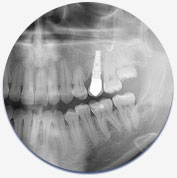

Dental Hygiene Dental Implants Cosmetic Dentistry Endodontics Restorative Dentistry Pediatric Dentistry Oral Surgery Emergency Care